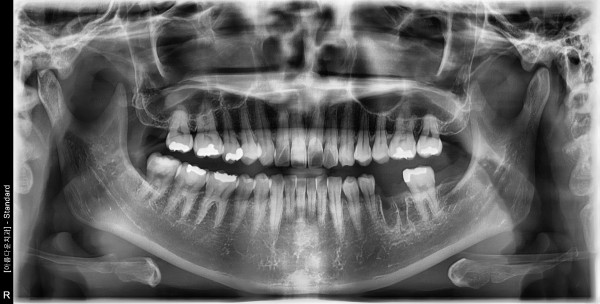

30대후반여성 / 왼쪽아래구치부 발치, 치조골이식, 임플란트식립